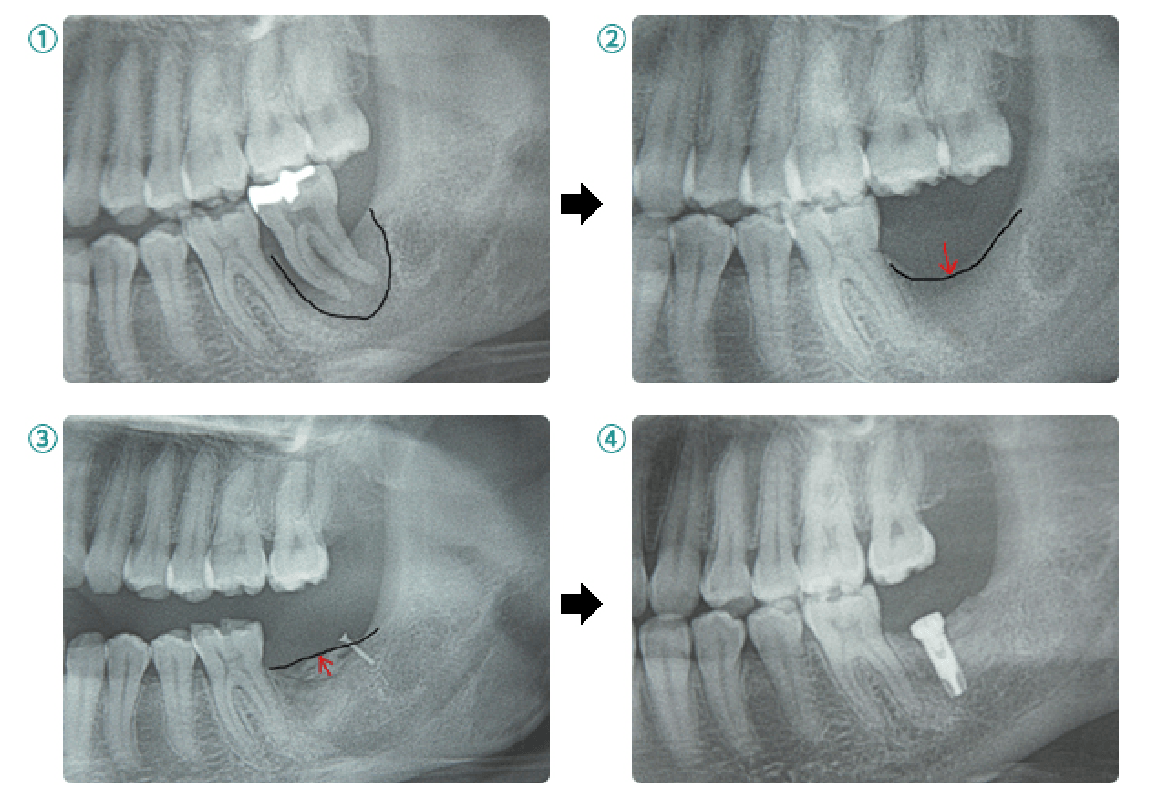

べニア(オンレー)グラフト

自家骨を用いた骨造成術の一つで、ブロック状あるいは板状に採取した骨をインプラント部位に移植して、チタン製スクリューで固定する方法。

ソケットリフトとサイナスリフト

上顎臼歯部には上顎洞(副鼻腔の一つ)が存在し、骨の高さが足りない場合があります。その場合、上顎洞底部の洞粘膜(シュナイダー膜)を挙上し、挙上によってできた空隙に骨移植を行い骨造成し、インプラントが埋入できるようにします。当院では骨の高さが5~6mm以上の場合にソケットリフト、5~6mm未満の場合にサイナスリフトを行います。つまり、たくさんの骨移植が必要な場合にはサイナスリフトになります。